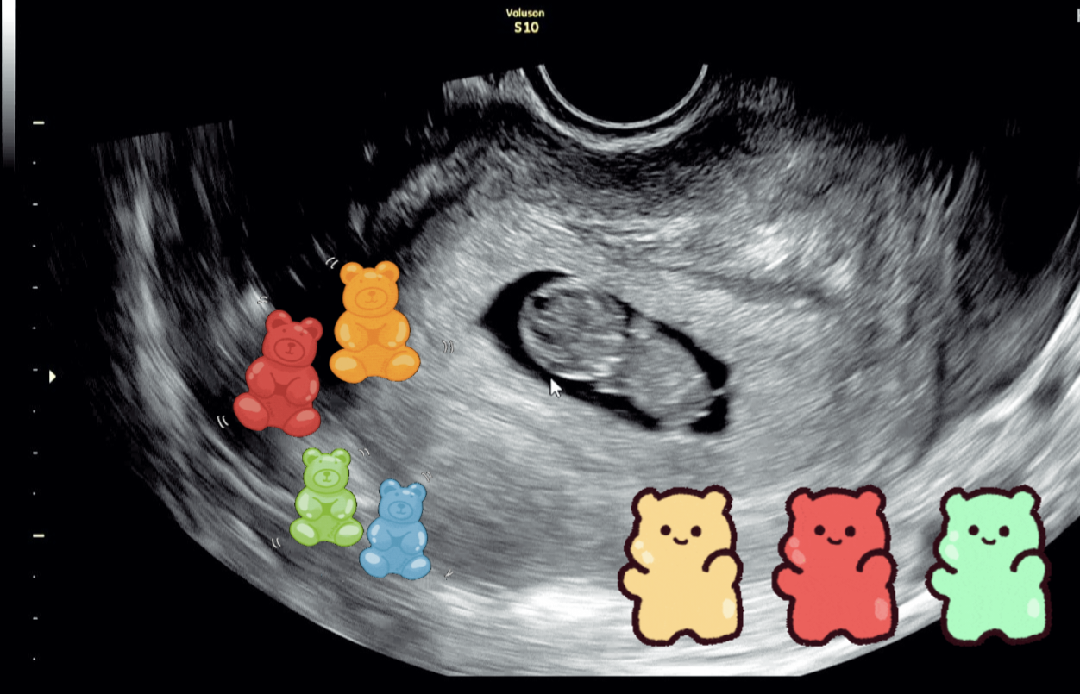

9주차! 초음파보고왓습니다 ㅎㅎ

쑥쑥 잘 크고있어서 마음 놓앗네요 ㅜㅜ ㅎㅎ다른 산모분들 아가들도 건강하고 쑥쑥 자라길❤ 다들 좋은 하루보내세용